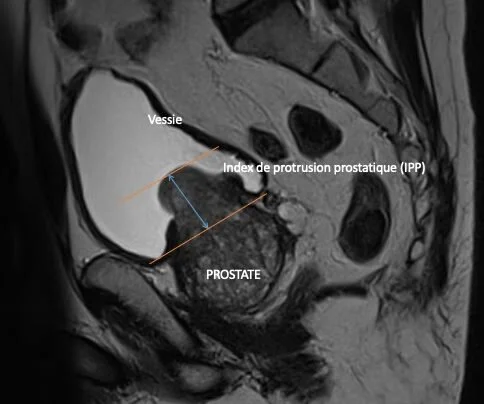

Image montrant une IRM de la région pelvienne mettant en évidence la vessie, la prostate et l'indice de protrusion prostatique (IPP).